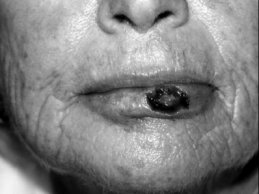

Small superficial defects limited to the vermillion may be allowed to heal by secondary intention with good results;1 however, larger or deeper defects or wounds near the vermillion border risk distortion if allowed to heal in this manner. Full-thickness grafts from the labial or buccal mucosa may be used, but often develop trapdoor deformity or mismatch color, texture, and thickness with the surrounding vermillion.

For defects approaching 50% of the vermillion width or greater, a complete vermillionectomy and mucosal advancement flap repair may be performed (Figures 1A–C). By removing the entire vermillion the risk of subsequent malignancy from adjacent actinic cheilitis is lessened, and the uniform repair and scarring help maintain symmetry of the lip. Like other repairs of the perioral area, mucosal advancement flaps should be marked out prior to the injection of local anesthesia. Mucosal advancement flaps are undermined below the level of the minor salivary glands, but above the orbicularis muscle. They are dissected back to a point where there is minimal closure tension at the vermillion border, and then closed by the rule of halves with absorbable and nonabsorbable sutures. While useful for large defects, mucosal advancement flaps have potential disadvantages. Advancement of mucosa to reconstruct vermillion often decreases the anterior-posterior dimension of the lip and can give a more rounded and reddish color to the reconstructed vermillion. Patients also frequently complain of persistent hypoesthesia, and men may note redirection of beard hair upward, causing irritation to the upper lip.

Another approach to vermillion repair for defects that are < 40% of the vermillion width is a bilateral vermillion rotation flap (Figures 2A–C).2 This flap utilizes adjacent vermillion to rotate centrally. The arcs of the rotation flap are drawn along the vermillion border with the redundant triangle of skin (dog ear) removed posteriorly. Back cuts are made at the oral commissures to permit rotation of the flaps and minimize pivotal restraint. Like the mucosal advancement flap, the bilateral vermillion rotation flap is undermined in a plane between the minor salivary glands and orbicularis muscle. This flap maintains the anterior-posterior dimension of the lip, avoids redirection of beard hairs, and decreases the risk of persistent hypoesthesia. This flap is an excellent alternative for repair of medium-sized defects in patients with less actinic damage to the adjacent vermillion.